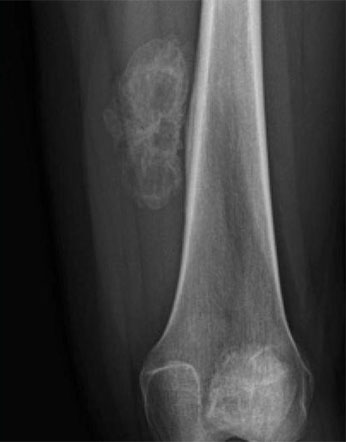

Опухоли костей являются редкими поражениями. Большая часть таких опухолей - доброкачественные образования, которые часто обнаруживаются случайно при радиологических исследованиях, проводимых по другим причинам. Что касается жалоб, они обычно проявляются отеком и болью. В редких случаях они обнаруживаются вследствие вызванного ими перелома в месте их расположения. Наиболее часто встречающимися доброкачественными образованиями являются остеоид-остеома, остеохондрома (экзостоз), энхондрома, неоссифицирующая фиброма, эозинофильная гранулема, простая костная киста, фиброзная дисплазия и внутрикостная липома / ганглия.